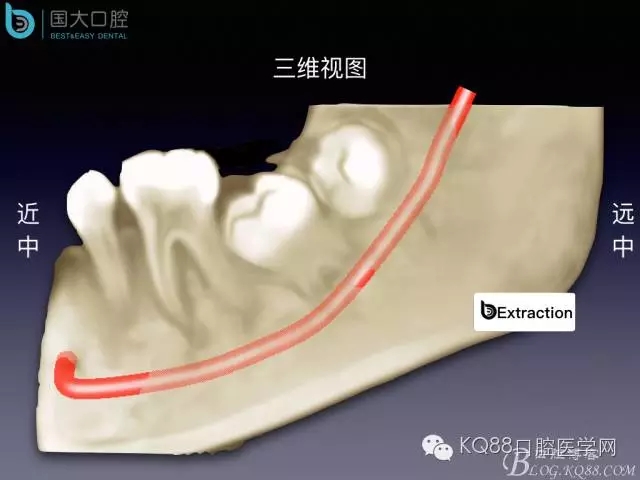

阻生牙的預(yù)防性拔除

- 牙齒拔除適應(yīng)證及第二磨牙遠中齲病